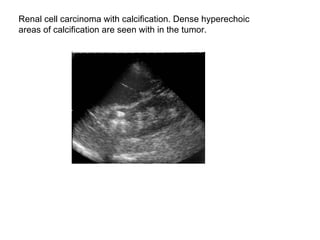

Renal cell carcinoma with calcification. Dense hyperechoic  areas of calcification are seen with in the tumor.